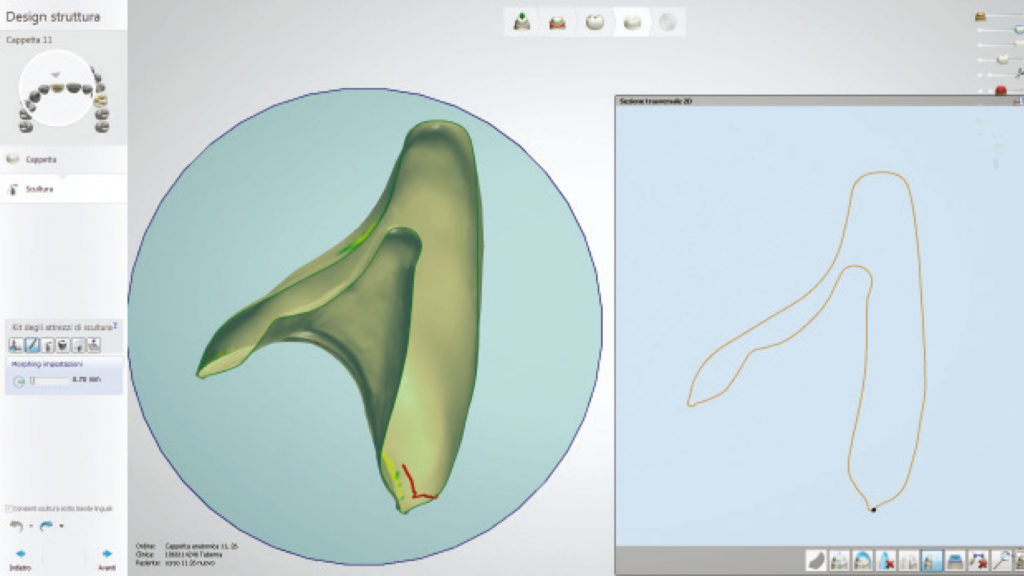

Für diesen Fall ist es von grundlegender Bedeutung, die vom Zahnarzt generierten Pfeiler, so exakt wie möglich zu replizieren, weshalb wir uns für den digitalen Weg entschieden haben (Abb. 27a und b).

In der Software können wir uns im Schnittbild die verfügbare Dicke der zukünftigen Kronen anzeigen lassen, woraus sich wichtige Schlüsse über die mechanische Festigkeit der Versorgung ableiten lassen (Abb. 28). Die Farbanalyse hat zudem ergeben, dass keine komplizierten internen Charakteristika reproduziert werden müssen, und ein ästhetisches Ergebnis leicht zu erreichen ist.

Auf diesen Beobachtungen baut die Wahl unserer vollkeramischen Versorgungsform auf. Die Platz- und somit Festigkeitsverhältnisse, in Kombination mit der relativ unkomplizierten Ästhetik, bestätigen, dass eine komplett vollanatomische Versorgungsform realisiert werden kann. Zum Einsatz kommt dafür das kubische und daher „ultrahochtransluzente“ (glasartige) Katana Zirconia UTML, dessen positive lichtoptische Eigenschaften sich für einen Fall wie diesen ideal ausnutzen lassen.